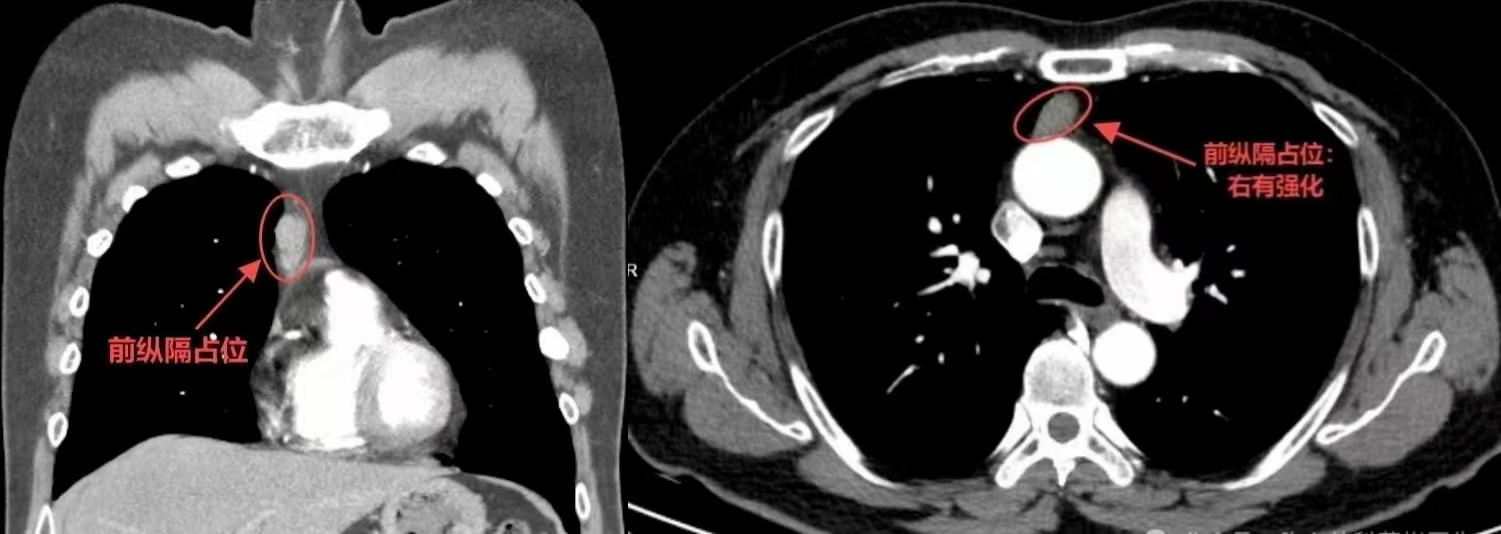

一次普通的体检,今年26的办公室职员刘先生(化姓),意外被查出胸部有个鹌鹑蛋大小的肿瘤,就是被称为胸腔“隐形杀手”的胸腺瘤。刘先生因此一度陷入焦虑,担心自己年纪轻轻,要面临开胸手术,留下难看的伤疤。为了打消刘先生的顾虑,三峡大学附属仁和医院胸心外科团队采用经剑突下“三孔式”前纵隔病变切除术,不开胸,仅用3个小孔就成功将肿瘤完整切除。

据了解,刘先生的病情并非毫无征兆。3个多月前,他突然感觉自己不太对劲,早上可以正常骑车上班,但一到傍晚,拿手机时手臂会颤抖,有时手机还会坠落。不仅如此,刘先生还发现自己的“眼皮睁不开”,最严重的时候还需要用胶带贴在眼皮上,让自己“强行睁眼”,看书时也出现重影,伏案工作时也感觉“脖子撑不住”,总想低头。“刘先生以为是自己工作压力大,身体劳累导致的,压根儿没想到是肿瘤引起。”胸心外科主任杨勇博士综合免疫指标和影像报告等各项检查分析后,认为刘先生的胸腺瘤符合肿瘤T3期特征,有侵袭性生长的趋势,必须要尽快实施手术。